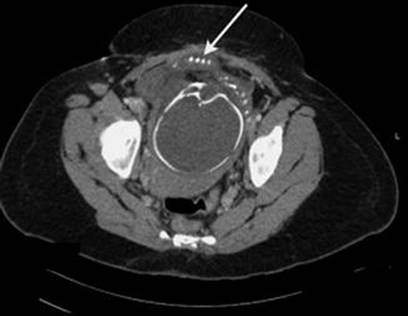

16.7.2 Abdominal CT

Abdominal CT scan should be done in unequivocal cases such as intestinal adhesions over uterine rupture delaying diagnosis. It is seen as focal disruption of the myometrium along with hemoperitoneum (Fig. 16.9). Other signs (see direct and indirect signs) such as fetal parts or hemoperitoneum outside of the uterus can be seen (Figs. 16.10, 16.11 and 16.12).

Fig. 16.12

A 34-year-old woman with seven previous Cesarean deliveries and a history of scant prenatal care presented at 32 weeks. The CT scan revealed a fetal hand protruding through the lower uterine segment (arrow) [210]